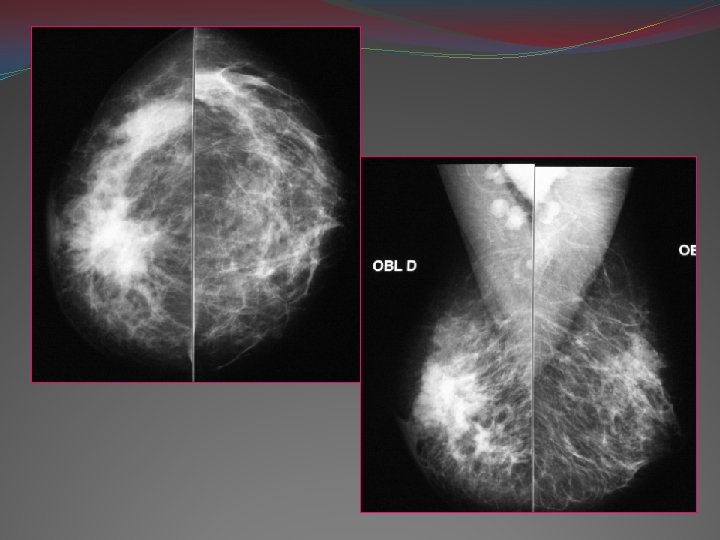

Moyens d’imagerie 1 -Mammographie: -Examen de référence: diagnostic, dépistage -1ère partie du cycle TECHNIQUE: Exploration toujours bilatérale, compression Incidences standards: face, profil, oblique

�Incidence oblique externe: Critères de réussite: Pectoral++ Sillon sous mammaire est visible Bande graisseuse rétro glandulaire visible

�Incidences complémentaires: -clichés de face tourné vers l’extérieur ou l’intérieur: examen des régions interne et externe -cliché tangentiel: M. e. e. des calcifications sous cutanées -cliché du prolongement axillaire -clichés centrés avec agrandissement: +++ orthogonaux ( face et profil), foyer fin de 0, 1 mm, fact d’agrandissement: 1, 5 - 2 Meilleur résolution des petites images Morphologie des micro calcifications -cliché avec compression localisée ++

2 -LES MICROCALCIFICATIONS: - Taille <1 mm de diamètre - Etiologies variables , révèlent plus que 50% des cancers infra cliniques - Isolées ou associées à un nodule - Pb diagnostic et de prise en charge - Cliché d’agrandissement +++ Analyse de la forme , de la répartition et de l’évolutivité

Type IV: Granulaires, irrégulières à angle aigus en « grain de sel » 50 -60% de cancers. carcinome canalaire in situ foyer triangulaire Foyer de microcalcifications dont plusieurs bifurquées (type IV). Histologie : comédocarcinome in situ.

Type V: Vermiculaires, en bâtonnets irréguliers coudés, bifurqués ou trifurqués, aspect (V, W, X, Y) disposition canalaire 90% de cancers

Microcalcifications typiques par leur morphologie (type V), leur polymorphisme et leur distribution (carcinome in situ) Foyer de microcalcifications de type IV et V, triangulaires, orientées vers le mamelon (comédocarcinome in situ). Calcifications très nombreuses, pathognomoniques (distribution en « raquettes » d’un carcinome intracanalaire.

v Analyse de la distribution: foyers ronds ou ovalaires bénignité foyers triangulaires ( sommet orienté vers le mamelon) Type IV et V Type V

Autres dispositions: - linéaires vers le mamelon « aspect en peau de serpent » Microcalcifications, granulaires, irrégulières, regroupées à grand axe linéaire orienté vers le mamelon (carcinome in situ) - Foyer avec encoches: « queue d’hirondelle » , « en papillon » microcalcifications vermiculaires peu nombreuses, agencées linéairement (carcinomein situ).

Disposition en raquette -plusieurs foyers: argument de plus de malignité +++

v. Polymorphisme des micro calcifications: forme, densité et taille différentes malignité Petit foyer sans disposition géométrique nette malignité vÉvolution : Polymorphisme et topographie suspecte Apparition d’une opacité associée Augmentation des micro calcif.